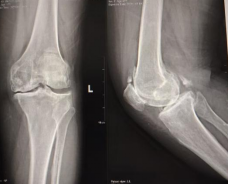

一年前,郭阿姨的左膝开始出现疼痛、活动不便。吃止痛药、打封闭针……各种方法都试过,效果却不理想。半年来,疼痛加剧,走路越来越困难,生活质量大打折扣。为求进一步治疗,遂来我院就诊,经诊断为「左侧膝关节骨性关节病」收治入院。

面对郭阿姨的病情,骨伤科主任张岩斌、副主任医师宋超带领团队高度重视。他们不仅为阿姨进行了详细检查,还组织了一场多学科(MDT)术前讨论,共同为她「量身定制」了科学、安全、个性化的手术方案。